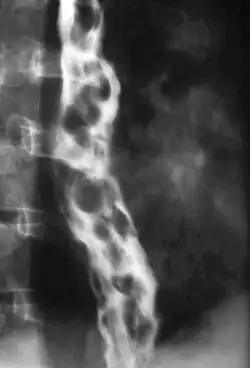

Esophageal varices are extremely dilated sub-mucosal veins in the lower third of the esophagus.[1] They are most often a consequence of portal hypertension,[2] commonly due to cirrhosis.[3] People with esophageal varices have a strong tendency to develop severe bleeding which left untreated can be fatal. Esophageal varices are typically diagnosed through an esophagogastroduodenoscopy.[4]

Dilated submucosal veins are the most prominent histologic feature of esophageal varices. The expansion of the submucosa leads to elevation of the mucosa above the surrounding tissue, which is apparent during endoscopy and is a key diagnostic feature. Evidence of recent variceal hemorrhage includes necrosis and ulceration of the mucosa. Evidence of past variceal hemorrhage includes inflammation and venous thrombosis.

Therapeutic endoscopy is considered the mainstay of urgent treatment. The two main therapeutic approaches are variceal ligation (banding) and sclerotherapy.

In cases of refractory bleeding, balloon tamponade with a Sengstaken–Blakemore tube may be necessary, or the use of a fully-covered esophageal self-expandable metallic stent, usually as a bridge to further endoscopy or treatment of the underlying cause of bleeding (i.e.: portal hypertension). Esophageal devascularization operations such as the Sugiura procedure can also be used to stop complicated bleeding. Methods of treating the portal hypertension include: transjugular intrahepatic portosystemic shunt (TIPS), distal splenorenal shunt procedure, or liver transplantation.